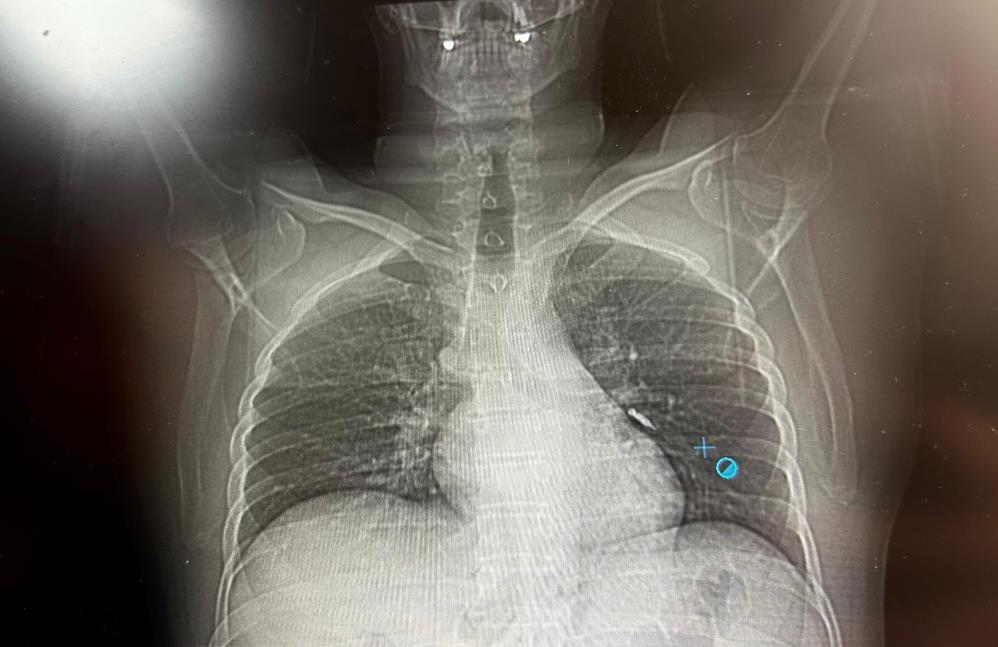

Van’ın İpekyolu ilçesinde ikamet eden F.T. isimli hasta, dış merkezli bir diş kliniğinde implant tedavisi gördüğü sırada, implant vidası yanlışlıkla soluk borusuna kaçtı. Nefes borusuna kaçan vida nedeniyle hasta, ileri tetkik ve tedavi amacıyla Van Eğitim ve Araştırma Hastanesi’ne sevk edildi.

Göğüs Cerrahisi uzmanları Dr. Sadullah Aksoy ve Dr. Beniz İrem Ersoy Şığva tarafından hastaya bronkoskopi işlemi uygulandı. Sol akciğerin üst lobunda saplanmış şekilde tespit edilen vida, vidalı yapısı ve bulunduğu konum nedeniyle güçlükle yerinden oynatılabildi. Yapılan uzun ve titiz müdahale sonrası vida yerinden çıkarılamasa da hasta bir süre sonra geçirdiği öksürükle birlikte implant vidasını midesine gönderdi. Vida, daha sonra doğal yollarla vücuttan atıldı.